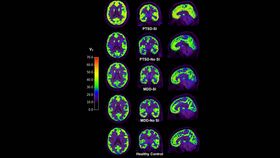

Dr Margaret Davis and other members of the Yale team compared 29 people with PTSD with another 29 suffering from major depressive disorder (MDD) and an equal number of mentally healthy controls. Half of both the MDD and PTSD group described feeling suicidal on the day the scan was taken.

Tests for depression are urgently being sought, but PET scans for mGluR5 are unlikely to provide them, as no noticeable difference could be seen between those with MDD, whether suicidal or not, and the controls. On the other hand, in Proceedings of the National Academy of Sciences Davis reports participants with PTSD had significantly higher mGluR5 availability in all five areas of the brain examined. The difference was entirely because of the subgroup of PTSD-sufferers experiencing suicidal thoughts that day, so that this subgroup stood out completely from all other participants.